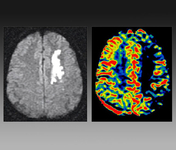

[图文]急性脑卒中,边看边学习

脑卒中是由于脑血管急性低灌注引起血管分布区域的脑组织发生缺血或出血,导致相应区域的缺血和神经系统功能的丧失。快速及时的诊断和治疗对于重建血运和恢复神经系统功能是十分有必要的。

脑卒中影像学鉴别诊断(一):灰质白质改变

影像学通常有助于诊断脑卒中,但是,大多数这些特征不是脑卒中所特有的。在本文中,我们将对脑卒中及其相似疾病进行分析。虽然仍存在重叠,这些分布类型有助于缩小鉴别诊断。